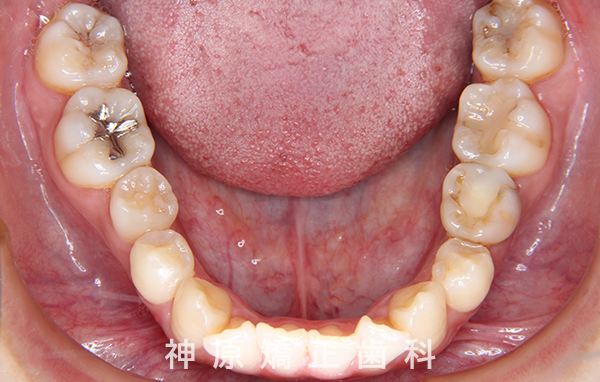

下顎:舌側矯正装置 - 抜歯 / 非抜歯

- 上顎左右第一小臼歯、

下顎右側第二小臼歯、下顎左側第二乳臼歯